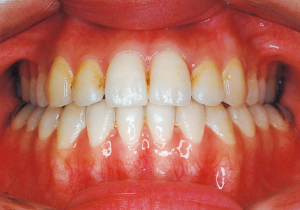

2 After Phase 2 Treatment 5-9-’92

16 5-9-’92 After Phase 2 Treatment

17 8-15-’94 After Retention 14 years and 7 months after start of treatment

Retention period: 2 years 5 months

Total Management Period: 15 years from 8 years 1 month to 23 years 1 month